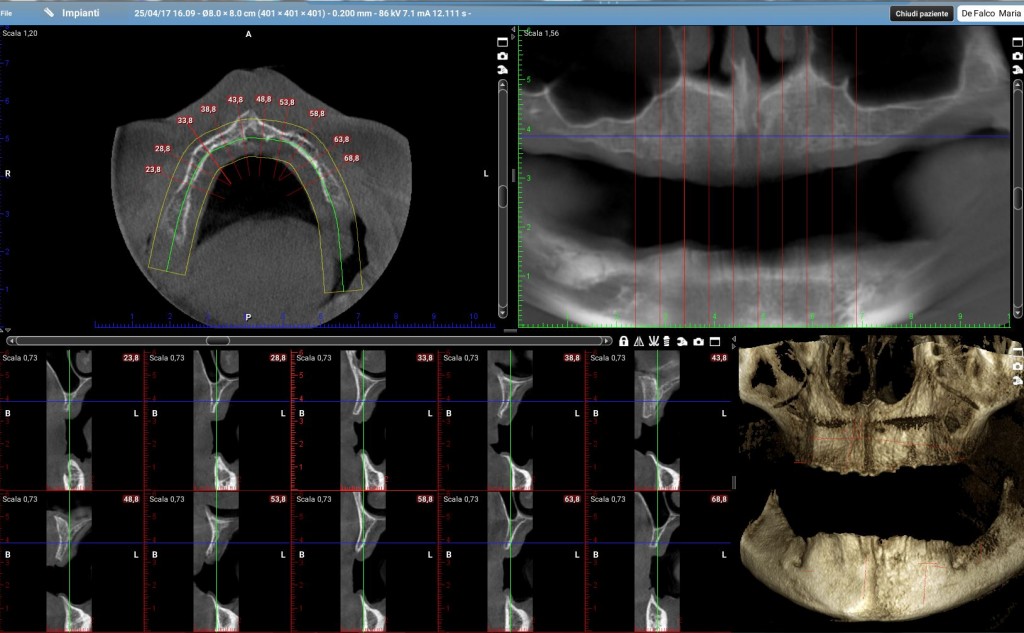

Durante l’ultimo corso di chirurgia Rocco (nome inventato) mi ha fatto vedere una cone-beam di un’arcata superiore; non ho la radiografia della sua paziente da usare come dato reale ma ti metto un mio caso concettualmente simile anche se un po’ più complesso.

Questa è la tomografia di una mia paziente.

Ora riprendiamo i tagli della cone-beam della mia paziente in corrispondenza delle zone dove dovrò posizionare i quattro impianti.